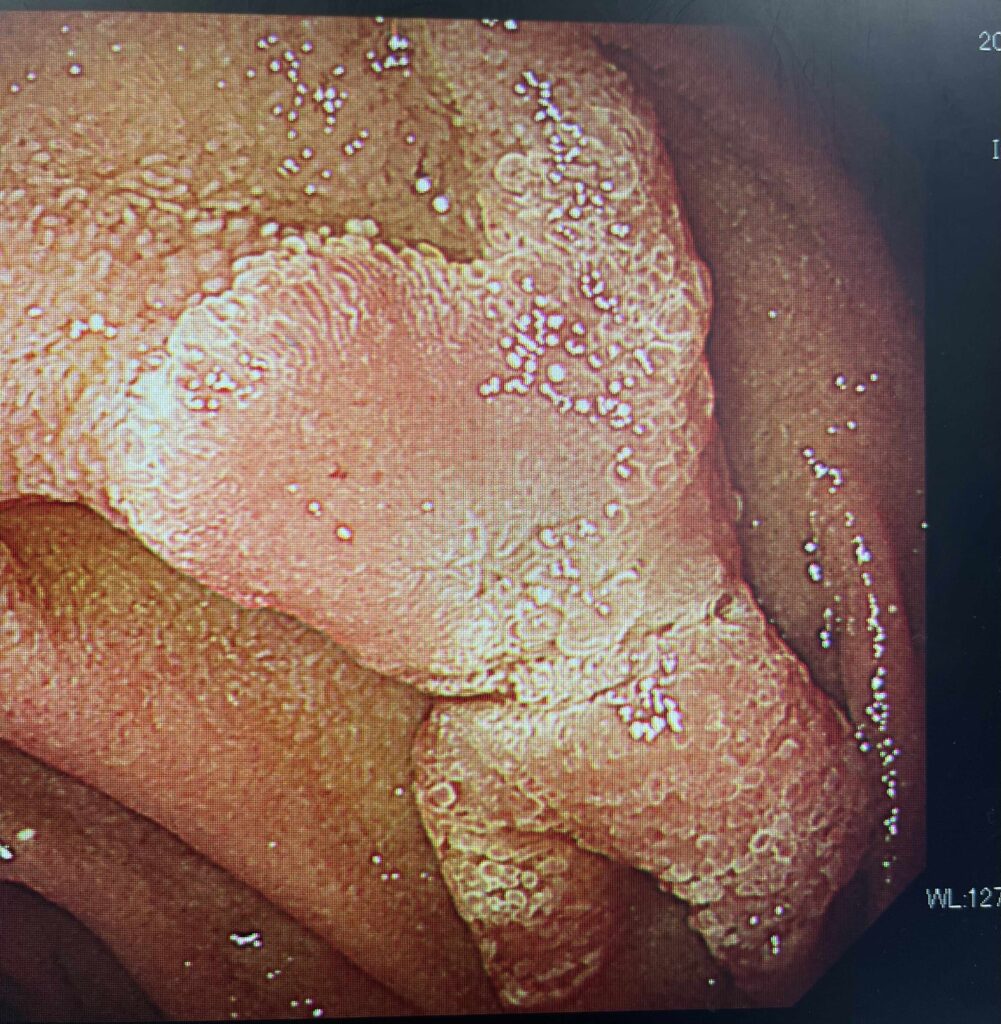

これらはすべて当院で無症状のうちに見つかり、内視鏡切除だったものです。

このような病変を見つけるためには無症状での早めの検査がすすめられます。

- 早期胃がんなら内視鏡治療(ESD)だけで完治できるケースが多い